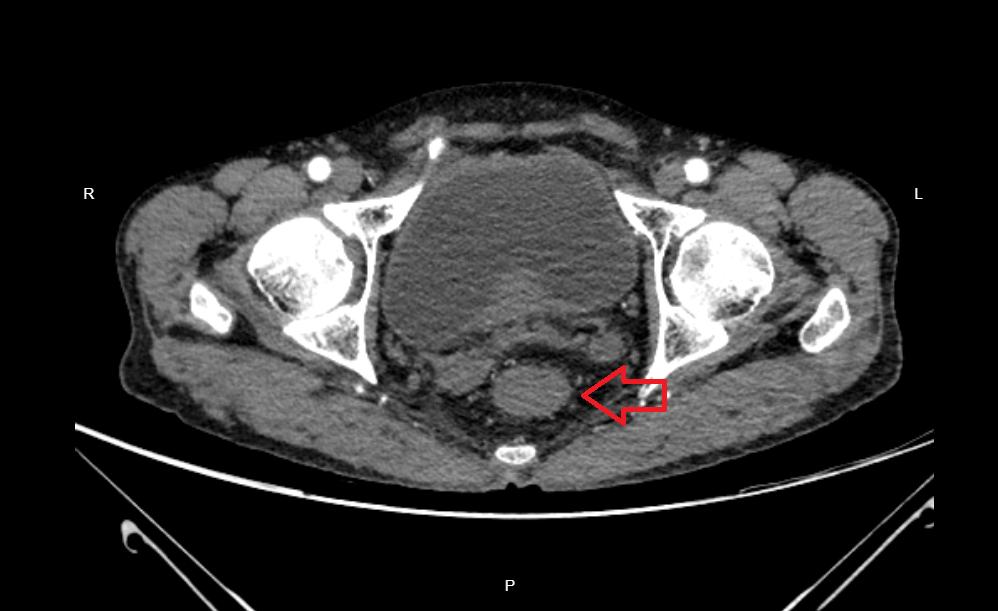

4月10日57岁的张叔叔因“大便习惯改变8月”到外一病区苟定奇医生处就医。CT提示直-乙交界段结肠壁不均匀增厚,增强后呈明显强化,考虑恶性肿瘤性病变,累及外壁、左侧肛提肌;肠镜下活检:(直肠粘膜)活检组织:腺癌。诊断:直肠恶性肿瘤(T4Bn1m0 ⅢC)伴梗阻。

为保证二期手术的成功,保障造口近端有足够长的肠段用于与直肠下段吻合,外一病区医疗团队术前细致评估影像资料,判断肿瘤范围,为患者行一期手术时选取了合适位置行乙状结肠双腔造口术,术毕转入肿瘤科进一步行放疗+卡培他滨化疗。

于7月8日患者按计划再次来院,经3月放化疗后增强CT及增强MRI均提示直肠上段肿物较4月明显减小,周围间隙清楚,适宜开展二期手术,7月14日手术过程中外一病区医疗团队竭力发挥腹腔镜手术优势,精准切除直肠肿瘤的同时予造口还纳,为患者避免了开腹扩大伤口或二次造口需三期手术的风险,整台手术耗时不到3小时,术中出血仅15-20ml,成功按计划完成了对患者的治疗。